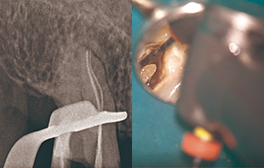

• Edge GlidePath™、EdgeTaper Platinum™、EdgeSequel Sapphire™を使用して二重湾曲根管の形状を残したまま、根管形成を行った例。

エッジグライドパスを使用

Edge GlidePath™

エッジテーパープラチナムを使用

EdgeTaper Platinum™ in MB

XPエンドシェイパーとエッジシークエルサファイアを使用

XP-Endo Shaper(白水貿易)+EdgeSequel Sapphire™ in MB1 & MB2

エッジシークエルサファイアを使用

#35/.04 EdgeSequel Sapphire™